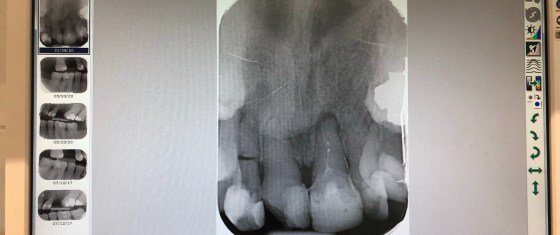

With Wendy’s tooth surgery pending the surgeon contacted me about who Wendys cardiologist was. Umm that was embarrassing as I…